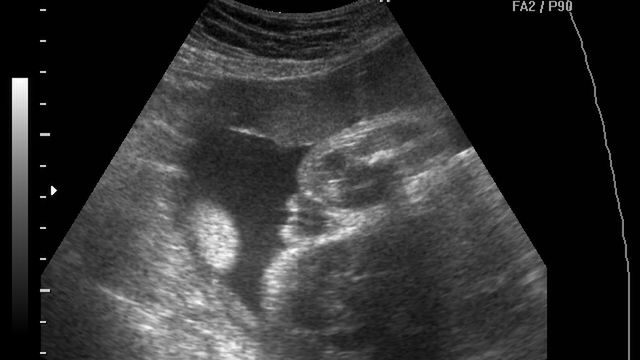

/ 10Zdjęcia płodu - 26 tydzień ciąży

Płód w 26 tygodniu ciąży, na zdjęciu widoczne męskie narządy płciowe